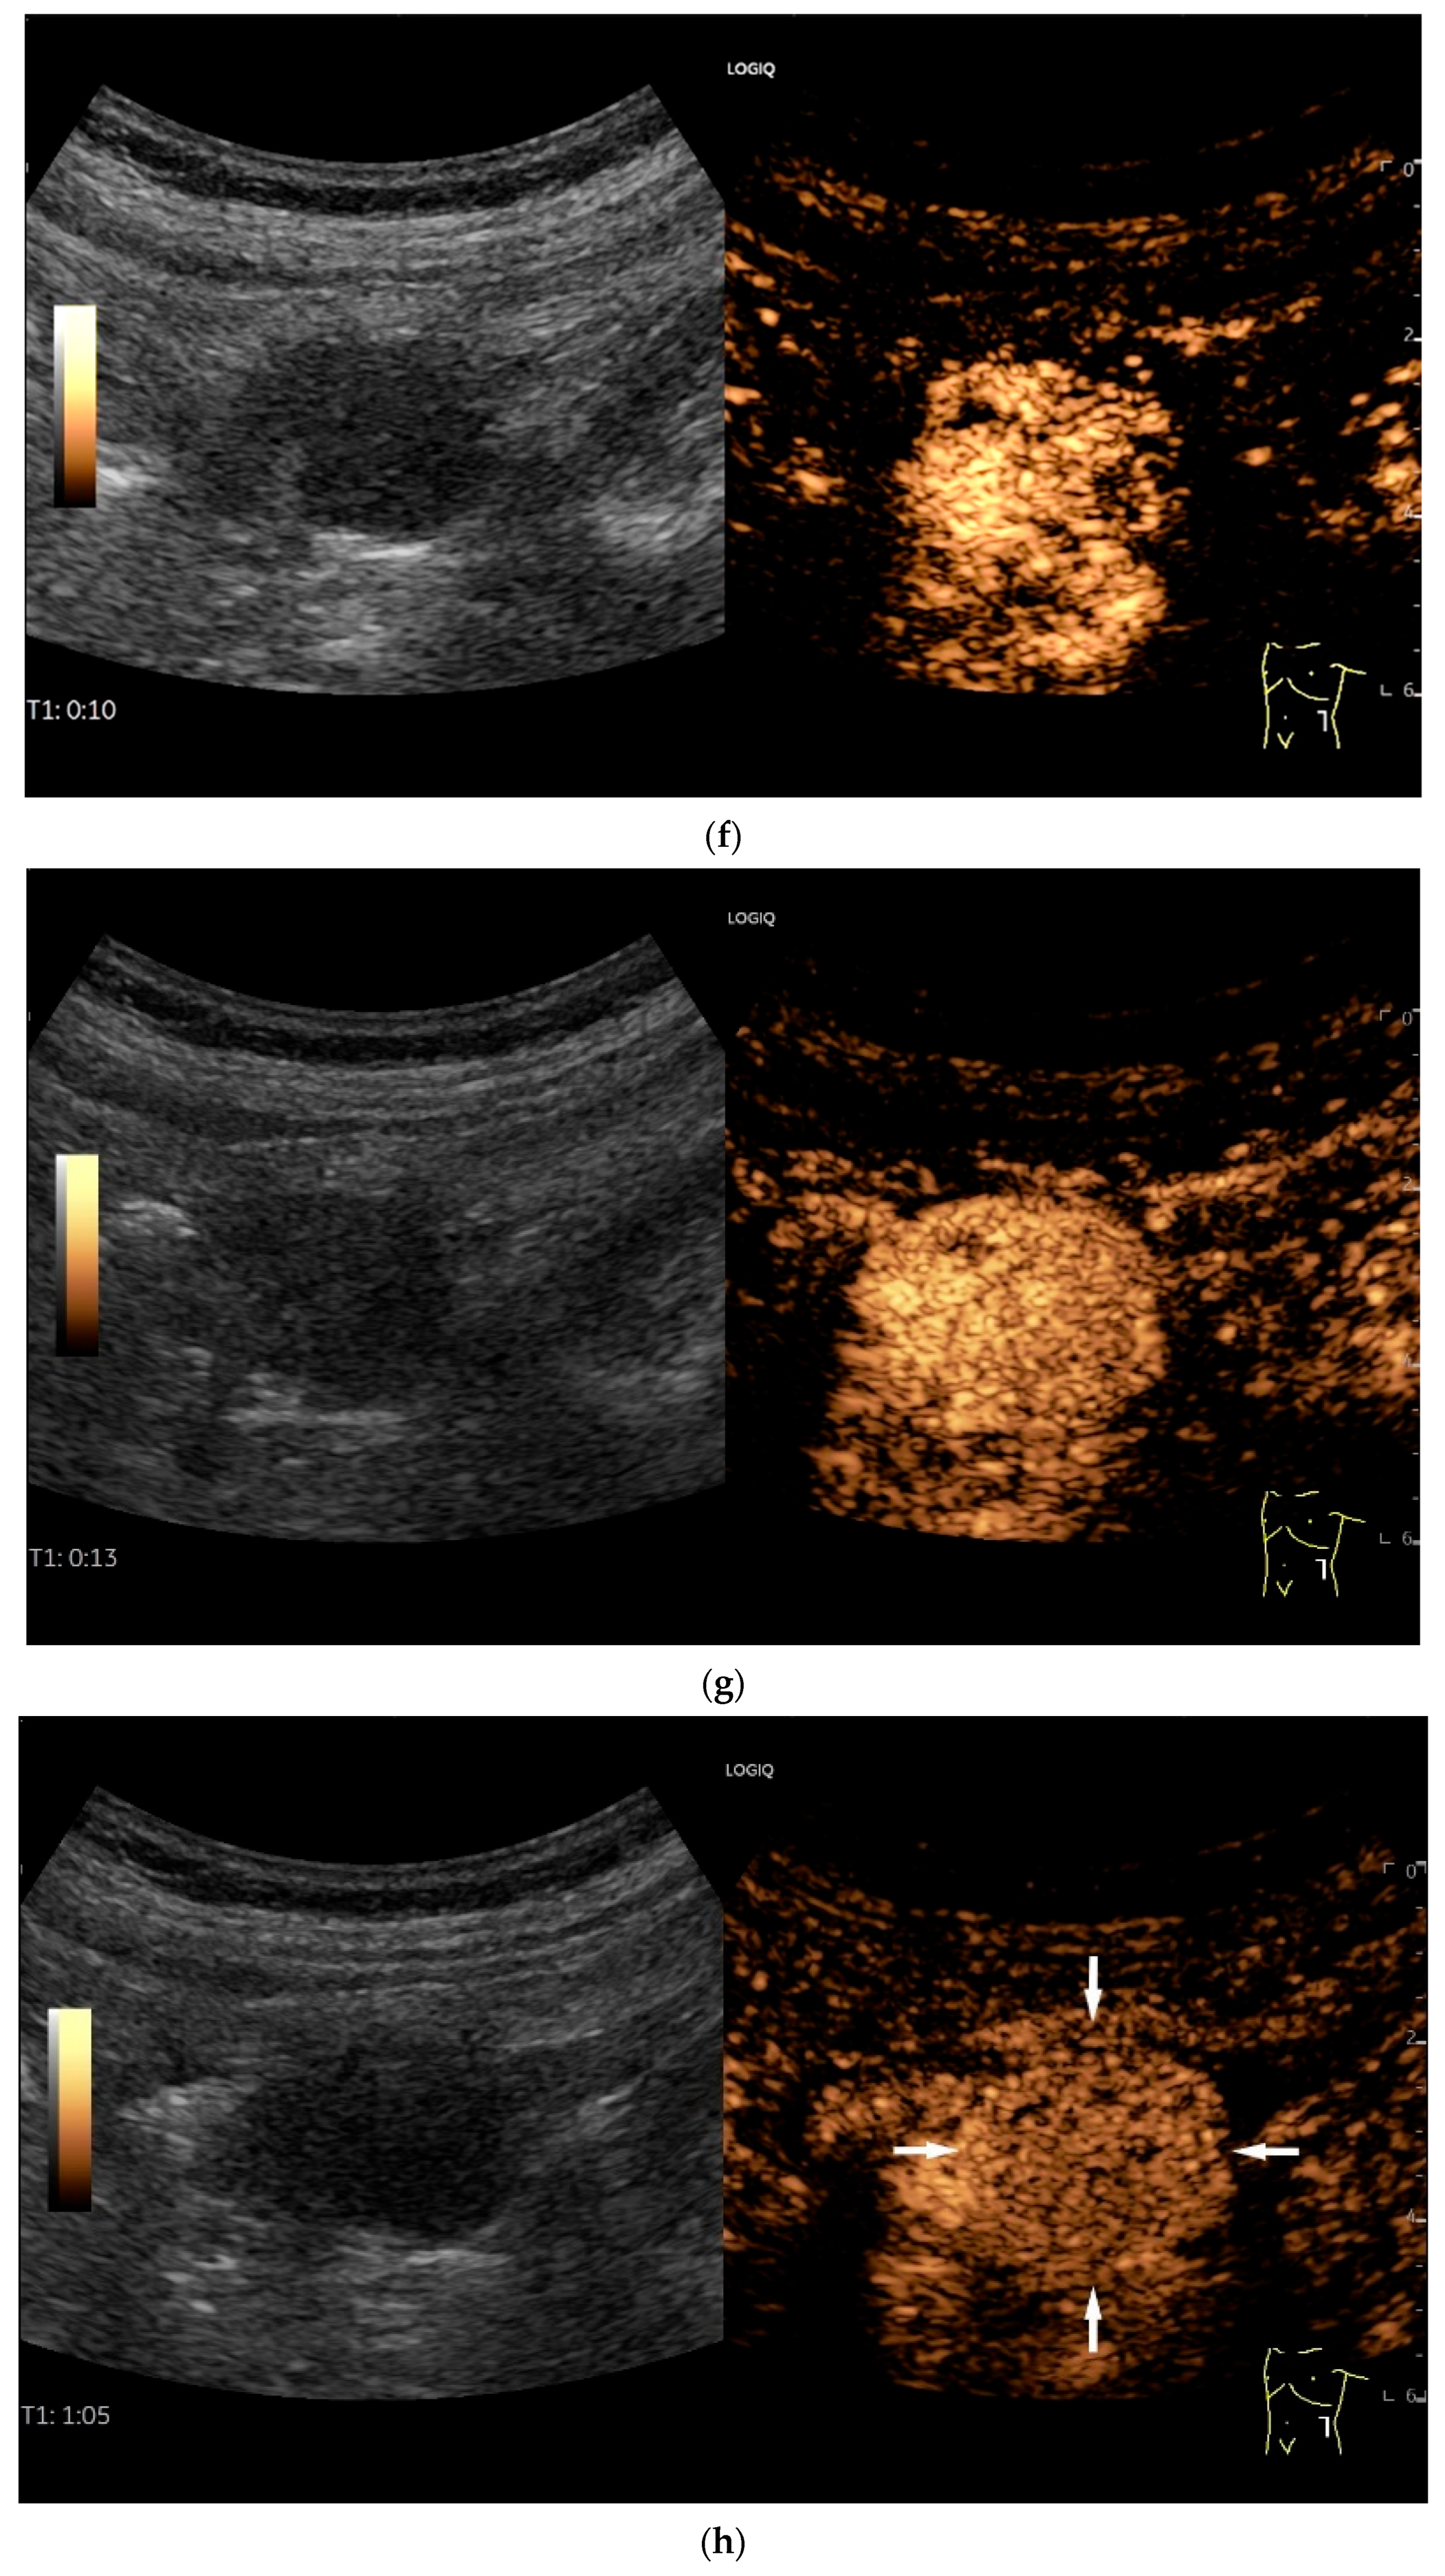

- Cui, N.Y.; Gong, X.T.; Tian, Y.T.; Wang, Y.; Zhang, R.; Liu, M.J.; Han, J.; Wang, B.; Yang, D. Contrast-enhanced ultrasound imaging for intestinal lymphoma. World J. Gastroenterol. 2021, 27, 5438–5447. [Google Scholar] [CrossRef]

| Lymphoma | Very pronounced wall thickening with marked hypoechogenicity. Large regional and distant lymph nodes. Look for splenic infiltration. Tumor vessels on CDI and hyperenhancement on CEUS. Heterogeneous hyperechogenicity of the mesentery with walling of the mesenteric vessels. Multiple localizations are possible. |